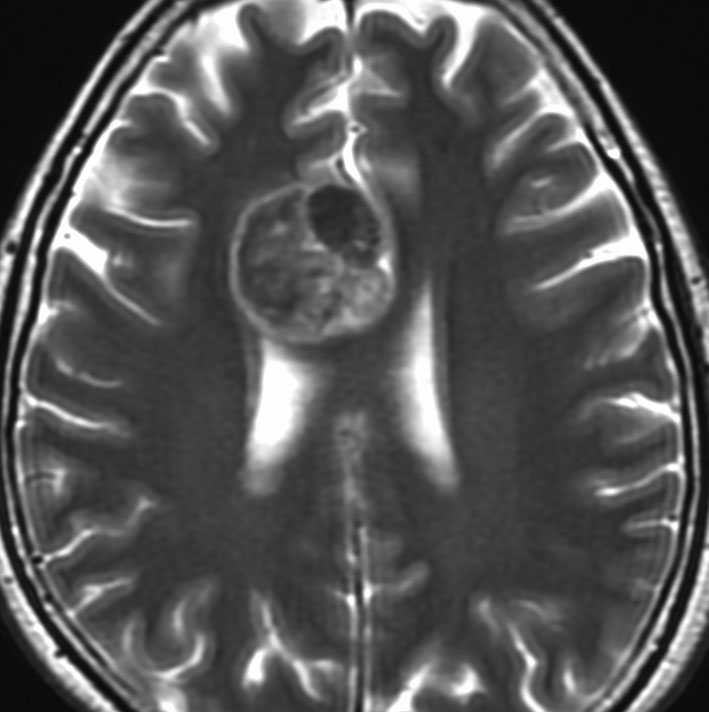

典型的な転移性脳腫瘍(単発)のMRI

腺癌の左前頭葉転移です。左のガドリニウム造影剤を使った画像では腫瘍が白く写っています。腫瘍の内部が一部壊死しているので黒っぽく見えます。右はフレア画像です。腫瘍の周囲の脳が腫れて脳浮腫(白く滲むようなところ)を生じています。

開頭手術で摘出した半年後の画像です。腫瘍は再発していなくて,脳の腫れも引いています。転移が発見された時には,見当識障害などの左前頭葉症状が強かったし,摘出がとても簡単な場所だったので手術しました。線状皮膚切開・小開頭ですから1時間くらいの簡単な手術です。でも,26mmくらいでしたから,定位放射線治療も可能なものでした。この患者さんは幸いなことに半年で再発していませんが,開頭手術による摘出だけだと同じ場所からまた再発することもあり,それから放射線治療を加えなくてはならないこともあります。個々の判断は難しいのですが,基本的には開頭手術より定位放射線治療のほうがいいと考えて下さい。